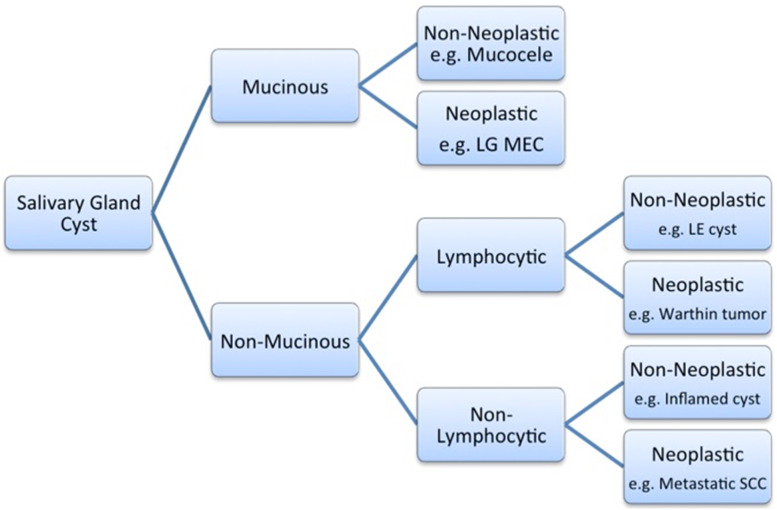

FNA of cystic lesions in the head and neck region is notoriously challenging because many disparate entities may present with similar cytological findings [10–12]. Moreover, FNA of cystic salivary gland lesions are typically of low cellularity. The rate of inadequate sampling and false negative results is increased in cystic lesions compared with solid tumors [13, 14]. The diagnostic value of FNA can be increased if, after drainage of cyst fluid, any residual solid components are also sampled. FNA may yield mucoid (mucin) or non-mucoid (e.g., serous) material. For this reason aspirates of cystic salivary gland lesions are typically divided into “mucinous” and “non-mucinous types” (Fig. 1). Mucin (mucicarmine-positive) may be viscous and resemble thick colloid-like material. Non-mucinous cyst contents are generally more watery, proteinaceous and may contain scattered acute and/or chronic inflammatory cells (e.g., lymphocytes, macrophages) and debris. Crystals may sometimes also be identified.

Fig. 1.

Flow diagram of a diagnostic approach to FNA of salivary gland cysts based on the microscopic presence of mucin associated with and without admixed lymphocytes. LG MEC low-grade mucoepidermoid carcinoma, LE lymphoepithelial, SCC squmous cell carcinoma

There is a broad differential diagnosis to consider when evaluating an FNA specimen obtained from a salivary gland cyst. The diagnostic approach recommended follows the algorithm depicted in Fig. 1.